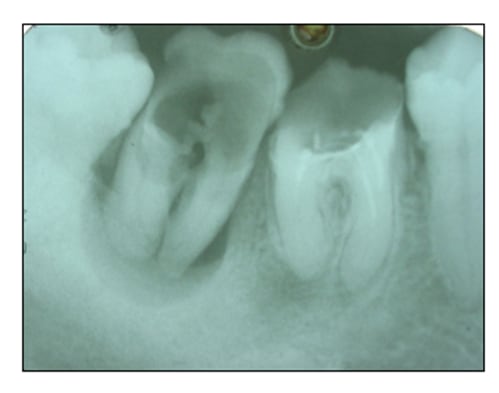

Et ça continue... (retour au moyen âge)

Ce patient avait bien mal à sa 28 depuis 3-4 jours... Il m'a gentiment demandé si je pouvais la lui enlever en urgence.

De profil elle paraissait pas difficile, je ne voyais pas grand chose mais les 8 du haut s'en vont facilement... le patient avait une toute petite ouverture, et des nausées rebelles qui m'ont(entre autre) empêchée de lui prendre une radio précise,(et qu'aurai-je vu?); pas de prise en vestibulaire, c'était tout carié.

Donc mobilisation en palatin après passage du syndesmotome , j'ai senti l'erreur quand l'ensemble est devenu souple assez rapidement...

Le gros problème a été de faire lâcher la gencive qui s'accrochait ferme sur la tubérosité qui flottait au fin fond du vestibule.

POur la photo,j'ai nettoyé et enlevé la charpie...